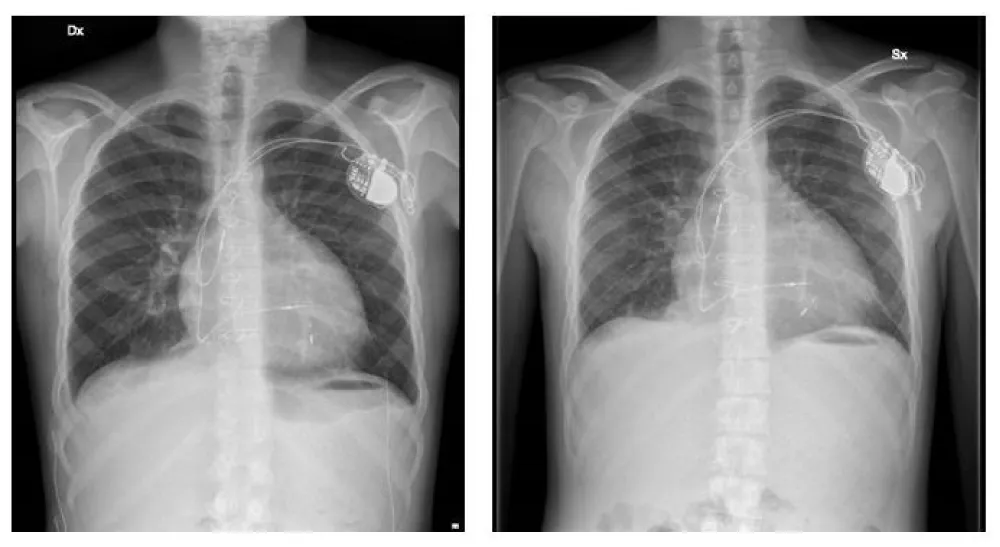

The standard extraction technique involved engaging the fragment with the snare, advancing an appropriately sized introducer over the snare under steady traction, and, once the fragment was fully enclosed within the introducer, applying additional traction to achieve complete retrieval. Ultimately, a 15-mm Lasso Snare was used to capture the remaining lead segment adherent to the subpulmonary free wall of the left ventricle. (video 3) With gentle, continuous traction, the fragment was advanced into the introducer and removed in a single piece. The procedure was completed uneventfully (Figure 2).

Final transthoracic echocardiography revealed no pericardial effusion. The Zurpaz introducer was removed following aspiration, and hemostasis was achieved by manual compression. Post-procedure chest radiography confirmed the absence of residual lead fragments. The patient was discharged in good clinical condition with a dual-chamber pacemaker programmed in DDD mode, demonstrating appropriate atrial sensing and capture. At one-year follow-up, fracture of the 6F atrial lead was detected. With the device programmed in VVIR mode, the patient maintained good functional status and excellent exercise tolerance. After having verified the patency of the superior venous axis, we’ll plan the extraction of the fractured lead and of the intact ventricular lead using a Liberator® Beacon® Tip Locking Stylet at the time of the next generator replacement (Figure 3). Furthermore, in the same procedure, the patient will undergo leadless pacemaker implantation. Leadless pacemakers have been developed to overcome many of the challenges of transvenous pacing, including complications related to leads or pacemaker pockets [5,6]. In fact, this patient experienced complications involving every type of implanted lead: infection of epicardial leads, fracture of an endocardial lumenless lead, and fracture of a conventional atrial lead.